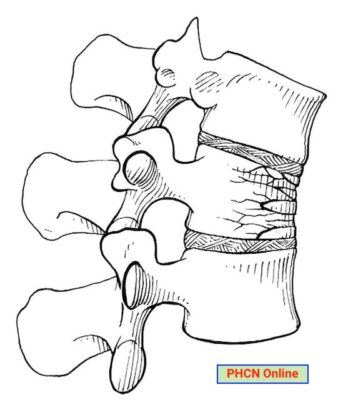

Gãy xẹp (hình chêm) cột sống ngực (đúng hơn là gãy do nén, compression fracture) là loại gãy gãy gây ra do lực nén ép thẳng trục hoặc lực gập. Đây là một gãy xương vững và hiếm khi bệnh nhân bị các tổn thương thần kinh.

- X quang ngực thẳng và nghiêng là xét nghiệm có giá trị chẩn đoán, phát hiện đốt sống bị giảm chiều cao, thường có dạng hình nêm, với chiều cao phía trước nhỏ hơn chiều cao đốt sống sau. Trong bệnh loãng xương, X quang cũng có thể phát hiện đốt sống bị biến dạng lõm hai mặt.